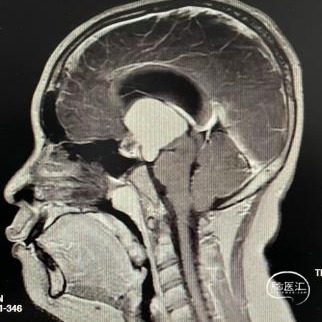

头部CT平扫显示:全鞍型蝶窦,鞍区-鞍上区-第三脑室可见一混杂密度肿块,内可见多发钙化灶,最大层面大小约43mm*35mm(左右径-前后径),CT值30HU,双侧脑室明显扩张,室旁可见对称性条片状低密度灶。

头部MRI显示:鞍区-鞍上区-第三脑室可见一不规则囊状长T1极长T2信号灶,大小约43mm*32mm*43mm,增强后可见病灶不均匀明显强化。垂体及视交叉未见显示,双侧脑室扩张,双侧脑室旁可见对称性斑片状长T1长T2信号灶。